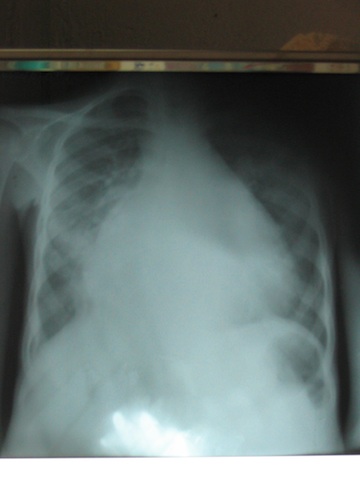

Medical 8-05 to 6-06

38 of 121